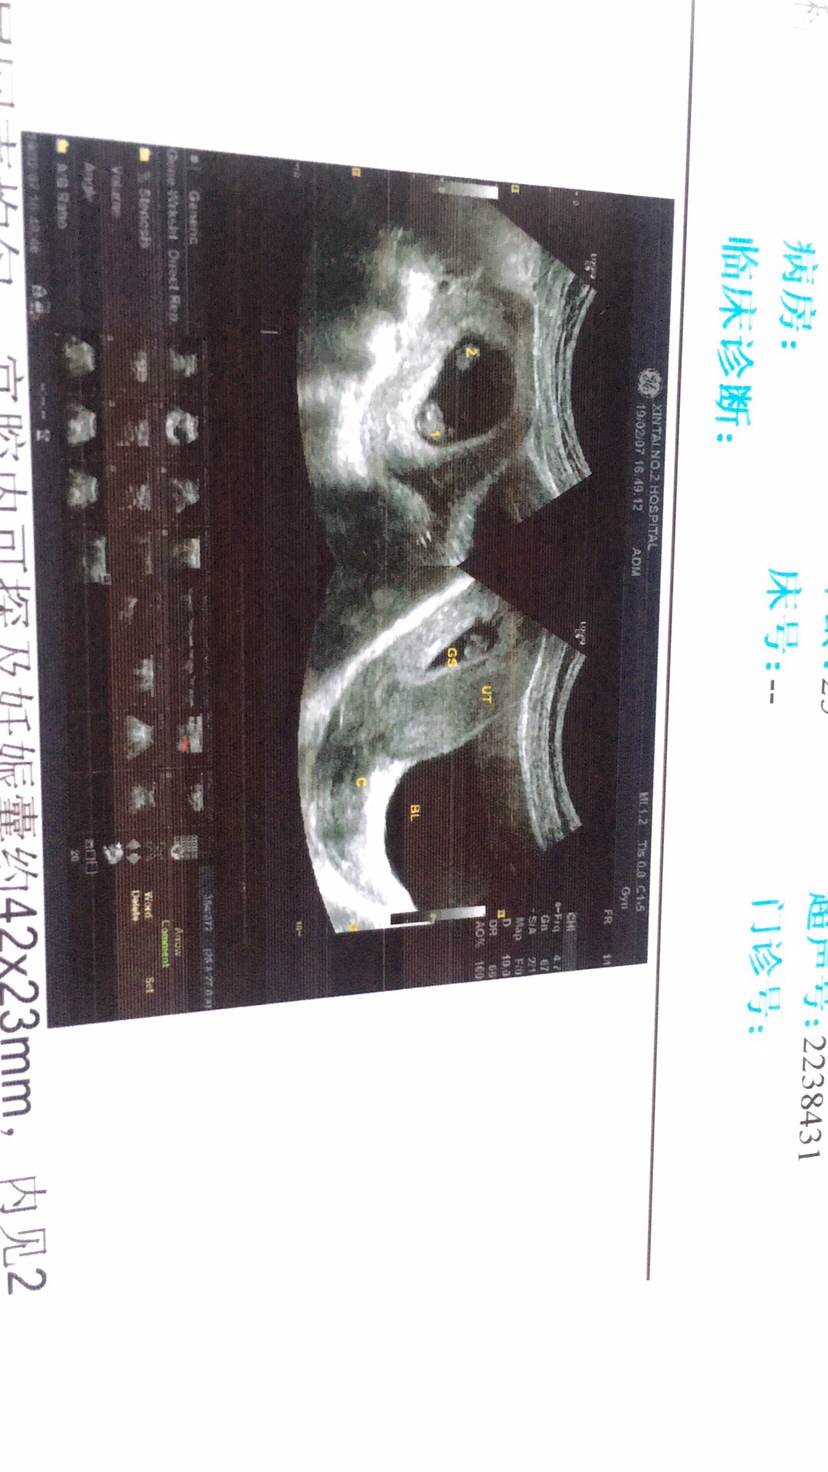

结果写的双胎